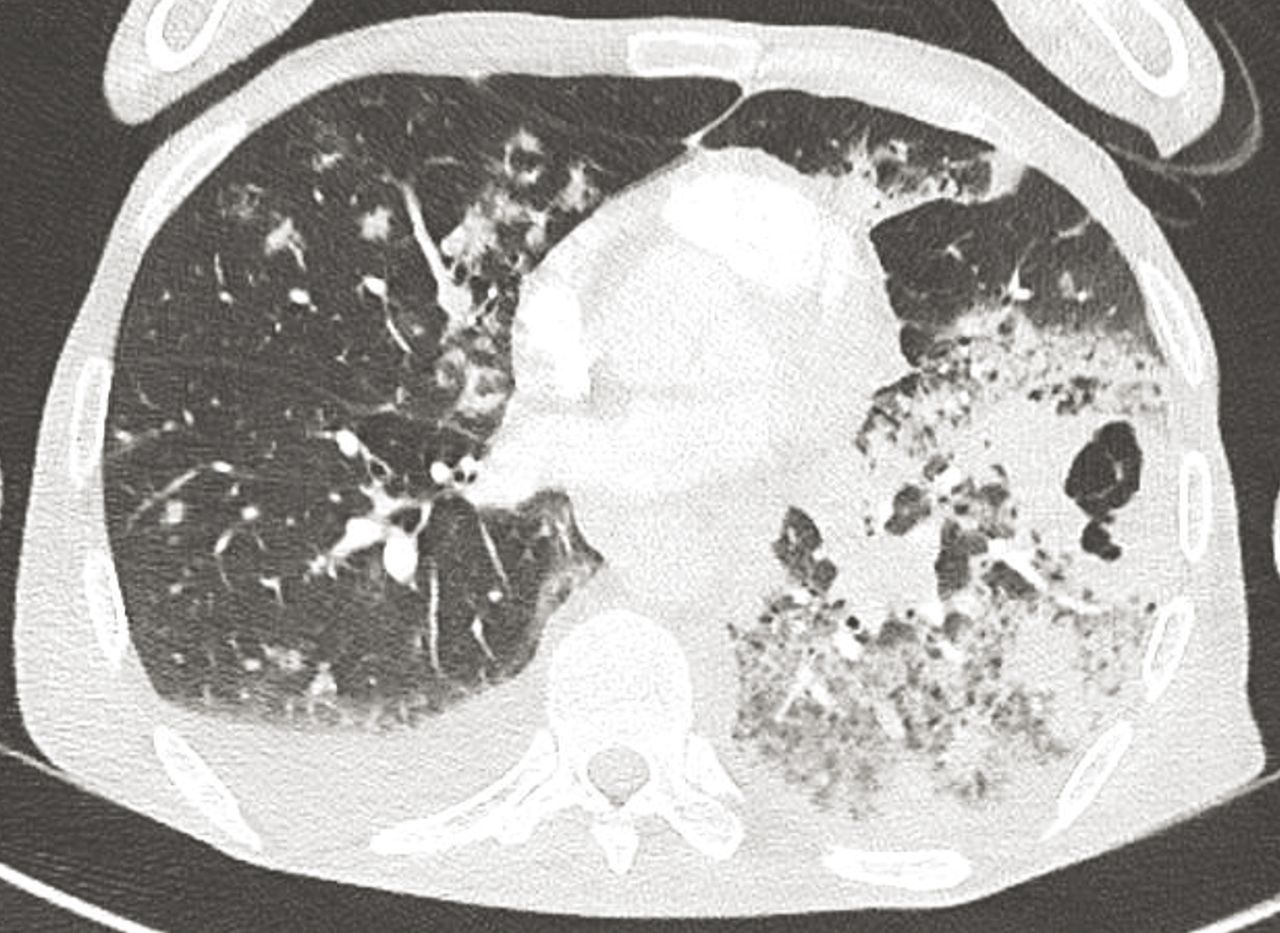

Homme de 56 ans , vivant dans des conditions précaires, tabagisme de 45 paquets-année, hospitalisé pour altération de l’état général et chute.

Quel est votre diagnostic ?